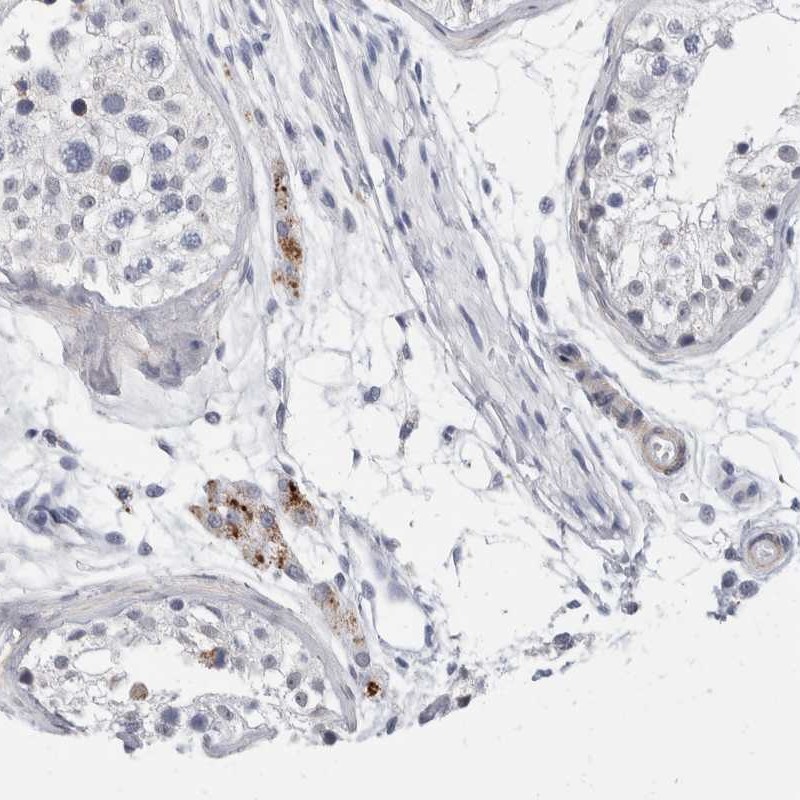

Immunohistochemical staining of human testis shows moderate cytoplasmic positivity in Leydig cells.